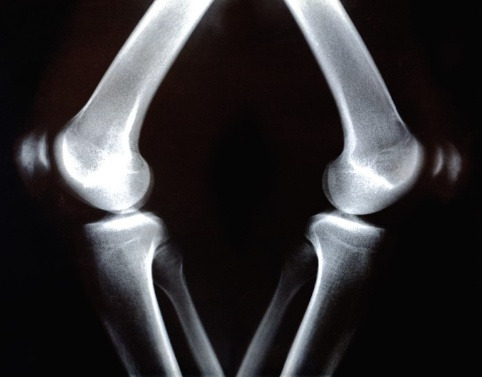

비타민D는 생체 내에서 다양하게 작용하는데 부족 시에는 골다공증, 구루병, 암(癌), 심장병, 뇌졸중, 당뇨, 근육통, 인지장애 등 다양한 질환의 원인이 될 수 있는 것으로 알려져 있습니다. 특히 골다공증과는 직접적 관련이 있는데, 비타민D는 칼슘, 마그네슘, 인 등의 미네랄의 흡수를 증가시키는데 중요하므로 비타민D 결핍 시 나타날 수 있는 증상 외에도 미네랄의 결핍 시에 나타날 수 있는 질환에도 영향을 미칩니다.

구루병.jpg 구루병

예로 칼슘의 흡수를 증가시켜 체내의 칼슘농도를 일정하게 유지시켜 골다공증을 예방하고 치료하는데 이용됩니다. 그러므로 칼슘을 같이 섭취하는 것이 좋습니다.

마지막으로 비타민D는 골다공증환자, 구루병환자, 야외활동이 적은 산모, 광부, 사무직종사자들에게 권장됩니다. 그리고 여성은 65세 이상, 남성은 70세 이상에서는 골밀도 검사를 시행하여 골다공증의 유무를 판단하여 골절을 예방하는 것이 좋습니다.